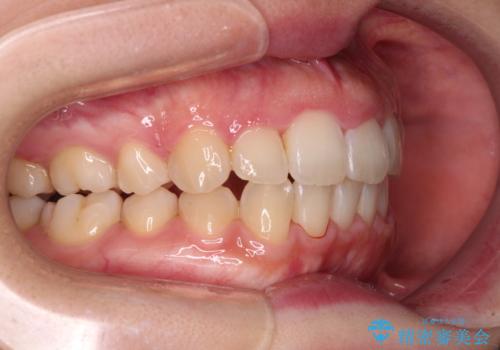

- 右上の八重歯と、左下八重歯を抜いてしまったことを気にして来院された患者様です。

下顎は既に犬歯を1本抜歯しているため、上顎右側第一小臼歯を抜歯し、ワイヤー装置にて歯列を整えることとしました。

変則的な抜歯となるため、正中と人中がずれる可能性がありましたが、仕上がりは上下正中を揃えることができました。